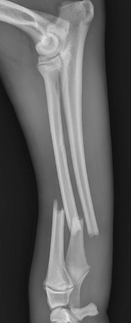

A fracture is a break in a bone. While often associated with major trauma, many fractures in dogs and cats actually occur from low-impact injuries. In these cases, the bones may be inherently too weak to withstand even minor forces. Classic examples include radius-ulna fractures (antebrachial fractures) in small breed dogs and elbow or humeral condylar fractures in breeds like French Bulldogs.

Fractures can vary widely — from partial (greenstick) fractures to severely shattered (comminuted) ones. Some fractures are open, meaning there is an associated wound. Others may occur secondary to underlying bone abnormalities, such as cancer.

Radiographs (X-rays) are the primary diagnostic tool and may require special views to fully understand the fracture configuration. CT imaging is particularly useful for complex or joint-involving fractures.